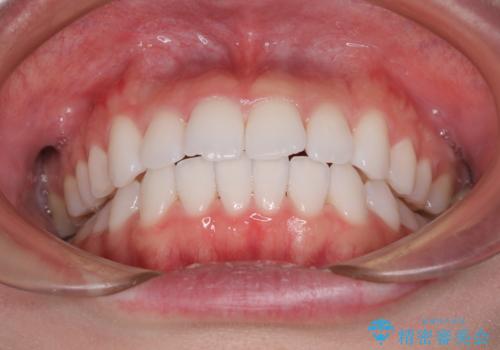

治療開始から4ヶ月ほどで概ね歯列が整い、その後の3ヶ月で細かい部分を仕上げていきました。

短期間で綺麗に仕上がり、患者様には大変満足していただきました。